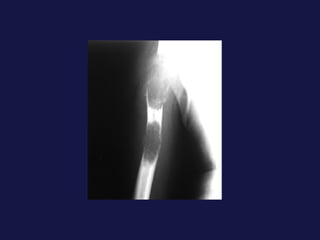

Metástasis. Cerebro. Hueso. Hígado. Suprarrenales.

Metástasis. Cerebro. Hueso.Hígado. Suprarrenales.